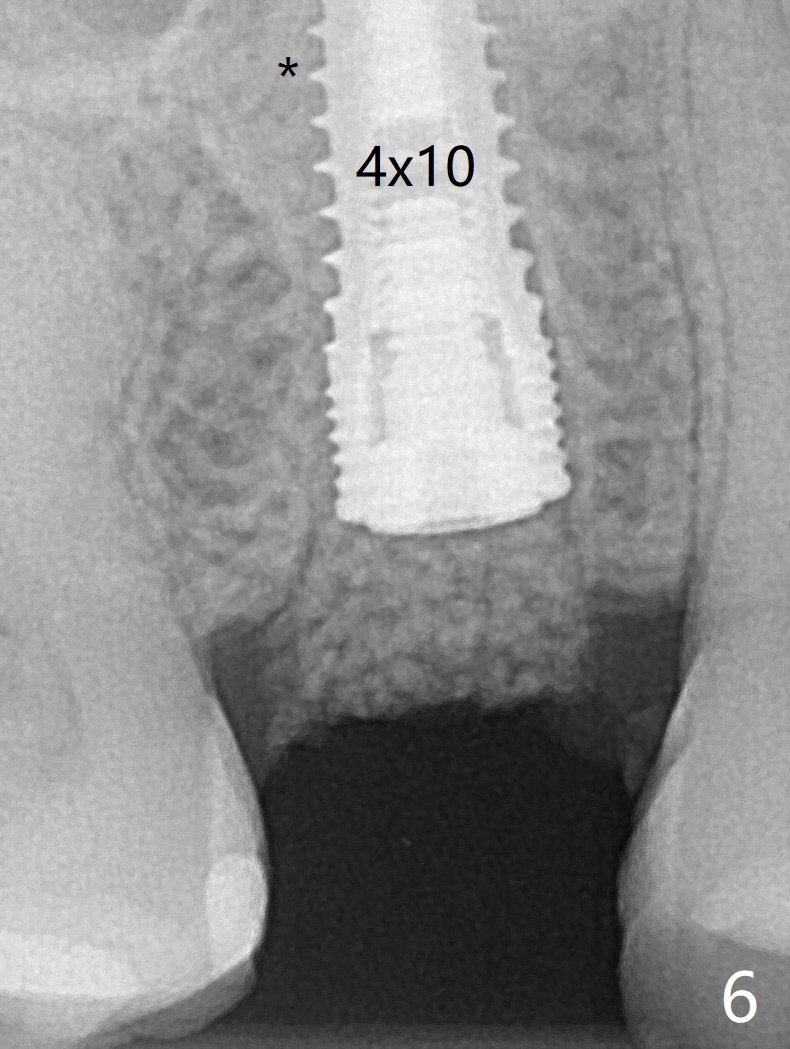

40岁女右上5近中龈下龋齿(图一),要求拔除植牙,上颌窦底板已经破坏穿孔,但是窦膜完整(图二)。清创后,放置PRF膜和粘性骨粉,用挖匙和上颌窦充填器尽量往上面推。然后放置导板,使用2.2x7.3 和3.0x7.3毫米钻头完成钻洞,可能无意中把骨粉推入上颌窦,之后利用报废植体(图三,四)完成提升,同时修补根尖缺损(利用之前放置的骨粉,图四:*,与图五(术前)对比)。当报废植体取出时,植牙窝已经形成,再放入少量骨粉,植入同样大小(之前扭力高)正式植体(不同品牌,图六,七),这时扭力低,放置愈合帽和骨粉(图七,八),以及6-9个月吸收膜,使用牙周胶水固定(图九),最后牙周敷料。术中术后几个小时没有上颌窦膜破裂迹象。术后一周牙周敷料松动,造成不适,去除时,膜好像粘附于敷料一起去除,骨粉暴露(图十),使用树脂敷料固定。后者术后一个月去除,因为局部有臭味。术后4个月切开放置愈合基台(图十一),术后五个月放置修复基台(图十二),使用塑料袖取模。术后5.5月同时放置牙冠和基台,十分顺手,口内粘固,之后同时取出,除去多余粘固剂,然后拧紧30Ncm(厂家推荐35 Ncm),一切非常顺利,觉得拍摄X光片是多余的。美中不足的是开孔(access hole)偏腭侧(图十二;由于自由手植入植体,与设计对比)。